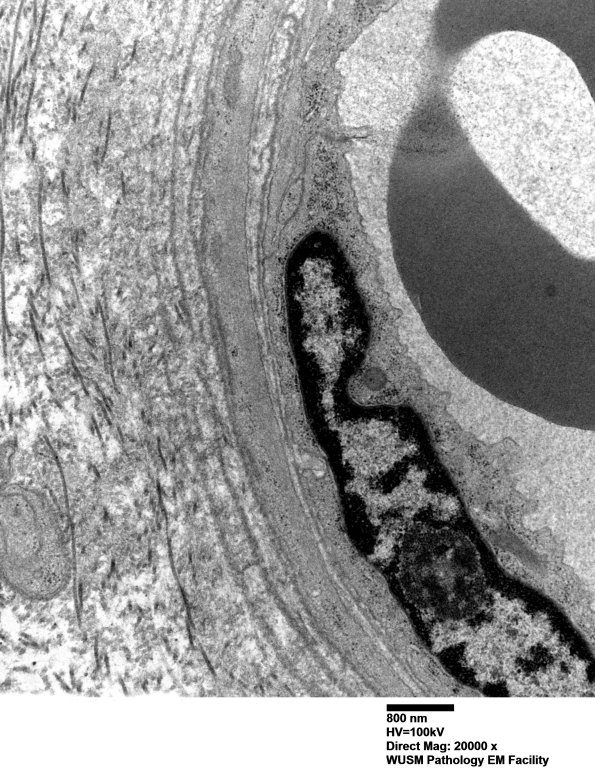

An additional example of mild vascular enlargement. (electron micrographs) ---- Interpretation: Mildly abnormal immune stains with C5b-9 staining of a few endoneurial capillaries. The changes are minor but could represent HIEM.